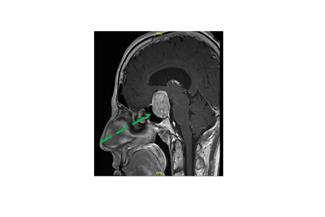

הניתוח לכריתת גידול במוח מסובך משום קרבתם של מרכזים חיוניים במוח והחשש לפגוע בהם. בשנים האחרונות פותחו טכנולוגיות מתוחכמות לעזרת המנתח, כולל דימות תלת-ממדי של הגידול, זיהוי אזורים חיוניים במוח שעלולים להיפגע במהלך הניתוח (MRI פונקציונלי), בקרת התפקוד של אזורי המוח, ומעקב באמצעי דימות בזמן אמת, במהלך הניתוח עצמו.